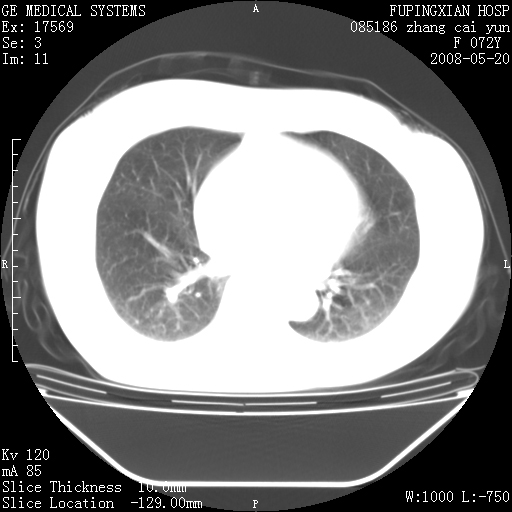

标题: CT13542:发热,咳嗽数日,经抗菌素治疗好转,请大家看排除 [打印本页]

标题: CT13542:发热,咳嗽数日,经抗菌素治疗好转,请大家看排除

右肺上叶实变影,内见支气管充气征,右上叶支气管通畅,肺门区未见软组织密度影,抗炎治疗有效,考虑炎症,建议继续抗炎治疗复查。

考虑为:右肺上叶感染性病变。建议:1)继续抗炎治疗后复查。2)必要时行纤支镜检查。

右肺上叶感染性病变。建议:1)继续抗炎治疗后复查。2)必要时行纤支镜检查。